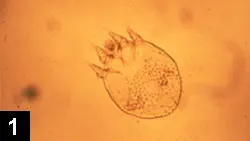

Sarcoptic Mange Profile Diagnosis Treatment